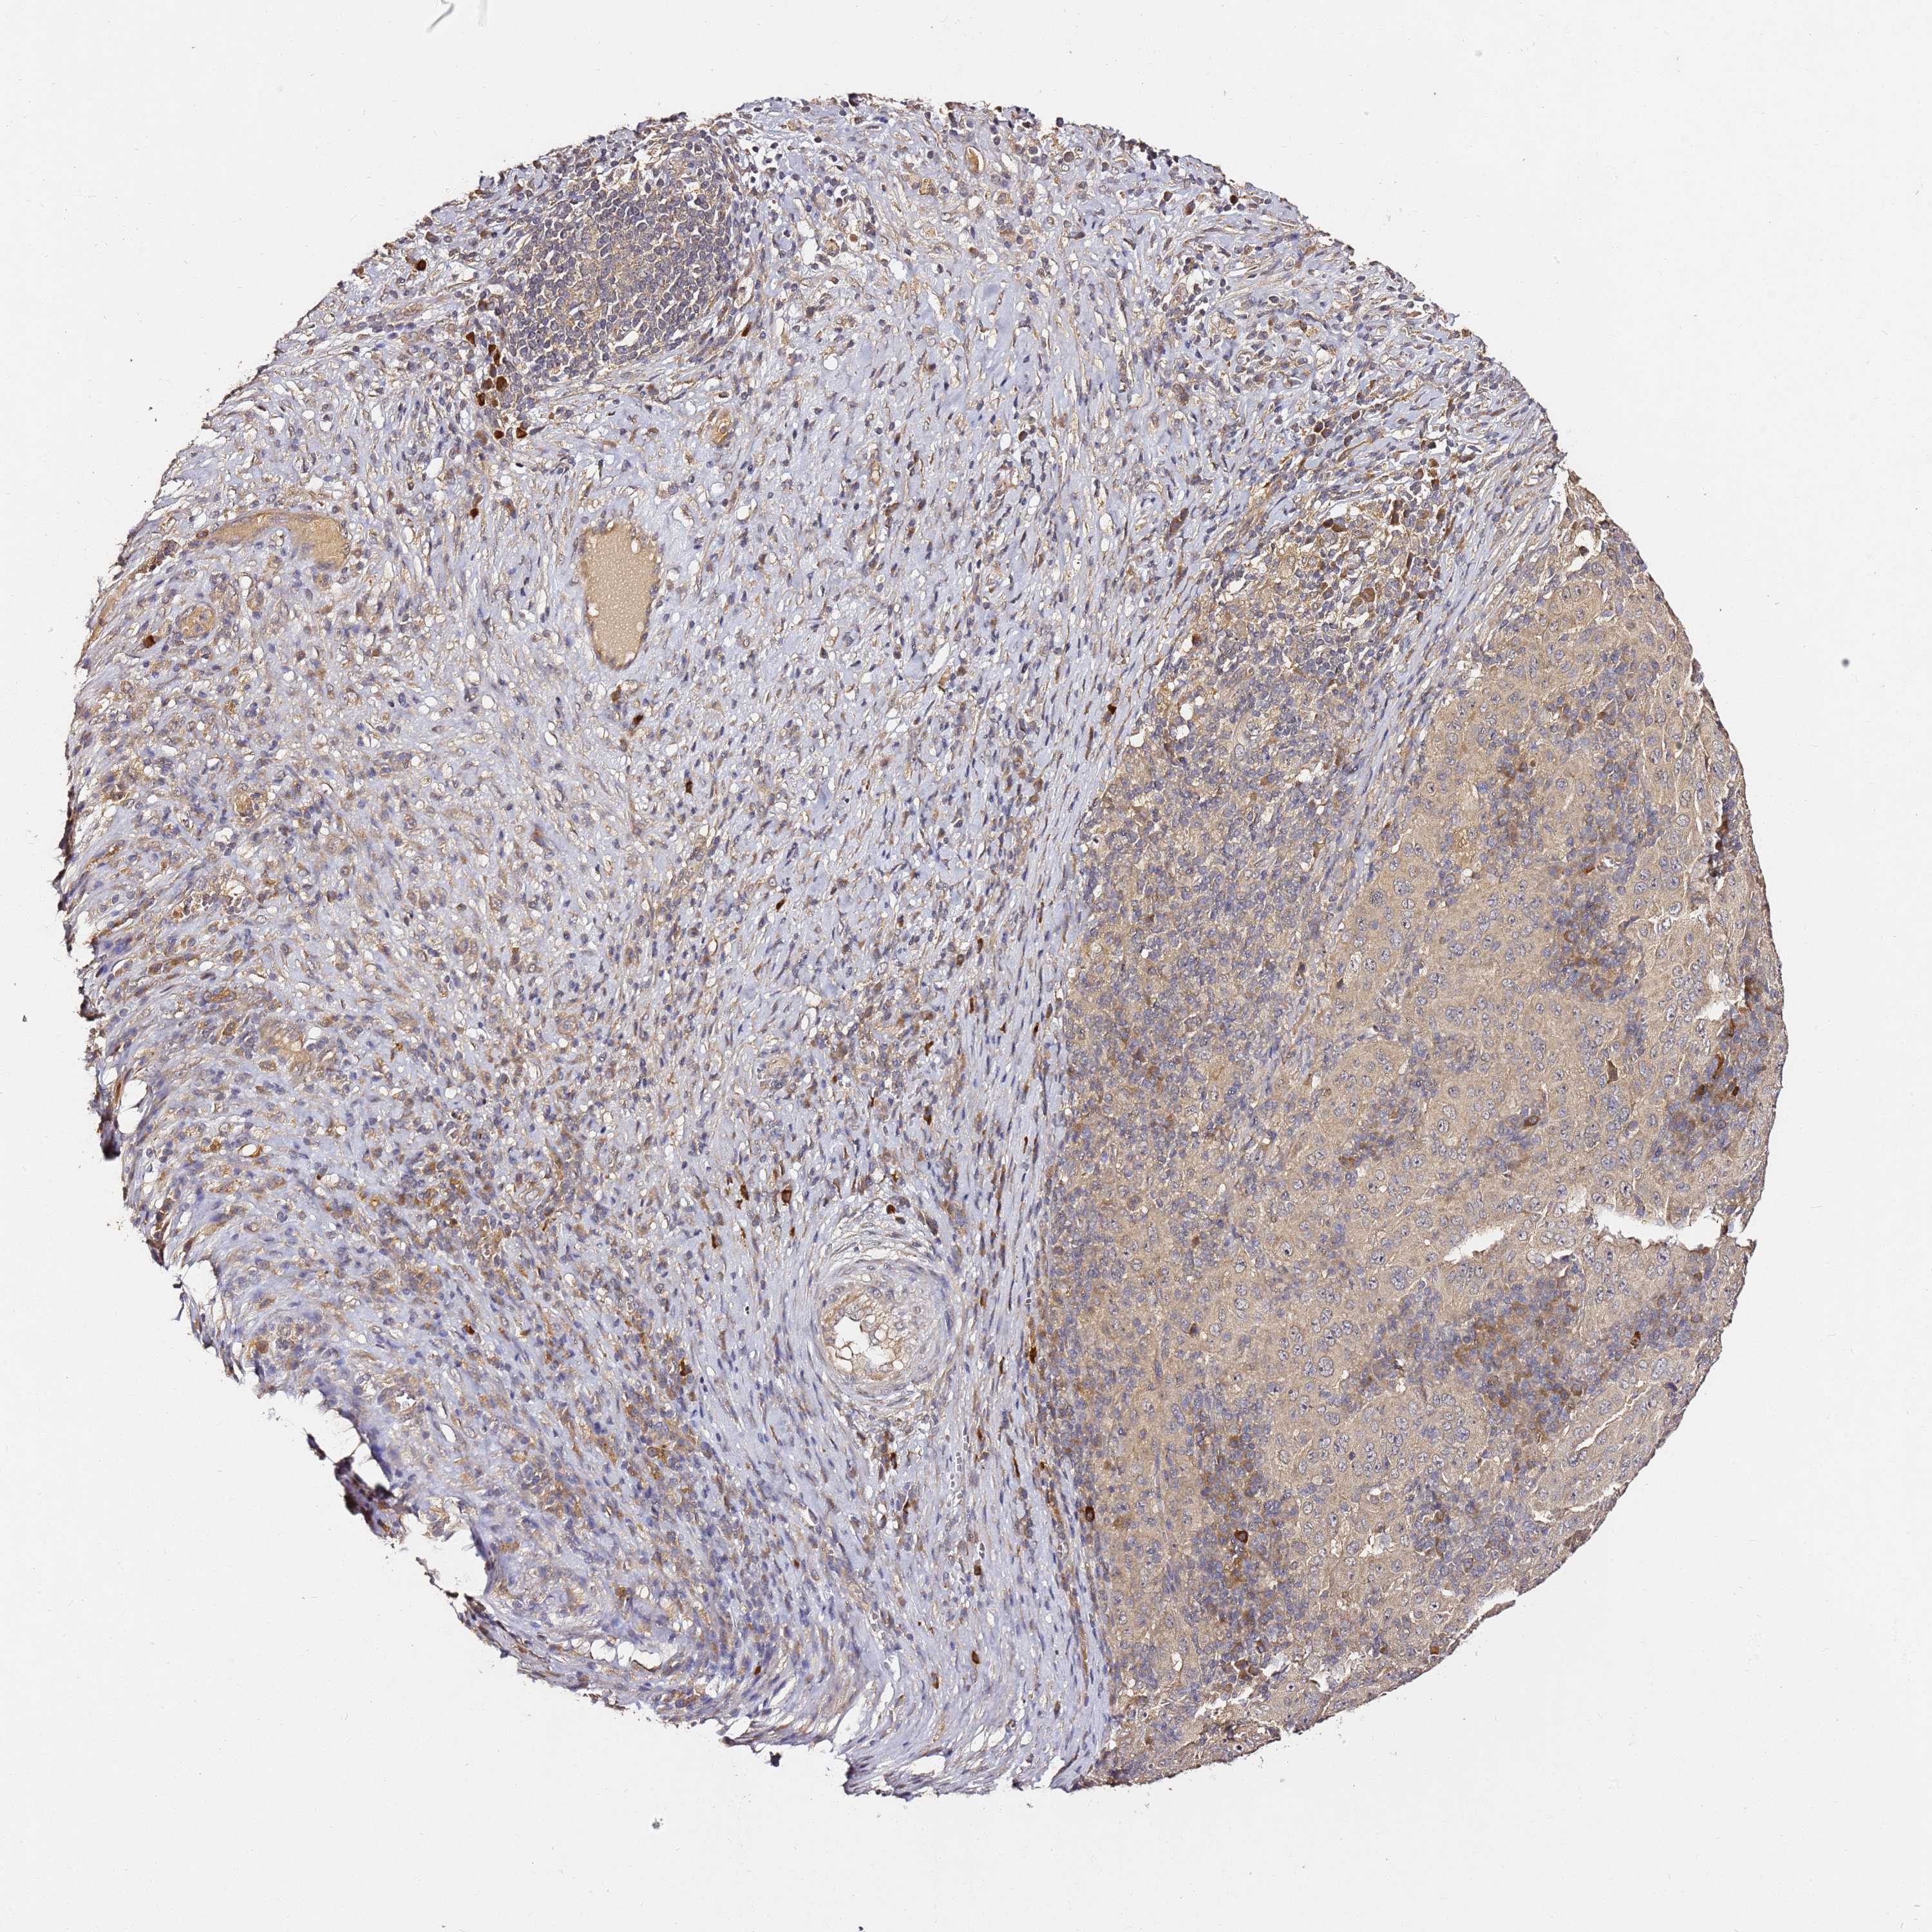

PANCREATIC CANCER - Protein expressioni

A mouse-over function shows sample information and annotation data. Click on an image to view it in a full screen mode. Samples can be filtered based on level of antibody staining by selecting one or several of the following categories: high, medium, low and not detected. The assay and annotation is described here.

Note that samples used for immunohistochemistry by the Human Protein Atlas do not correspond to samples in the TCGA dataset.

Antibody stainingi

Antibody staining in the annotated cell types in the current human tissue is reported as not detected, low, medium, or high, based on conventional immunohistochemistry profiling in selected tissues. This score is based on the combination of the staining intensity and fraction of stained cells.

Each image is clickable and will lead to virtual microscopy that enables deeper exploration of all samples and also displays staining intensity scores, fraction scores and subcellular localization as well as patient and tissue information for each sample.

Antibody HPA046804

Staining

High

Medium

Low

Not detected

Intensity

Strong

Moderate

Weak

Negative

Quantity

>75%

75%-25%

<25%

None

Location

Nuclear

Cytoplasmic/membranous

Cytoplasmic/membranous,nuclear

Adenocarcinoma, NOS